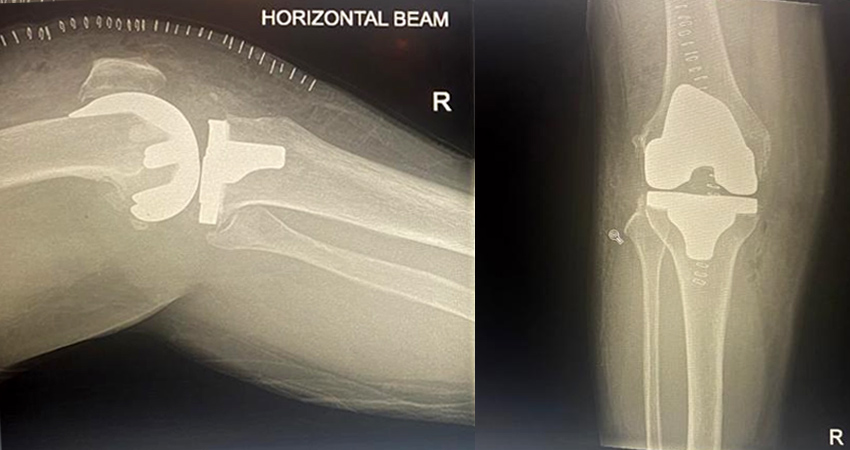

Total Knee Replacement